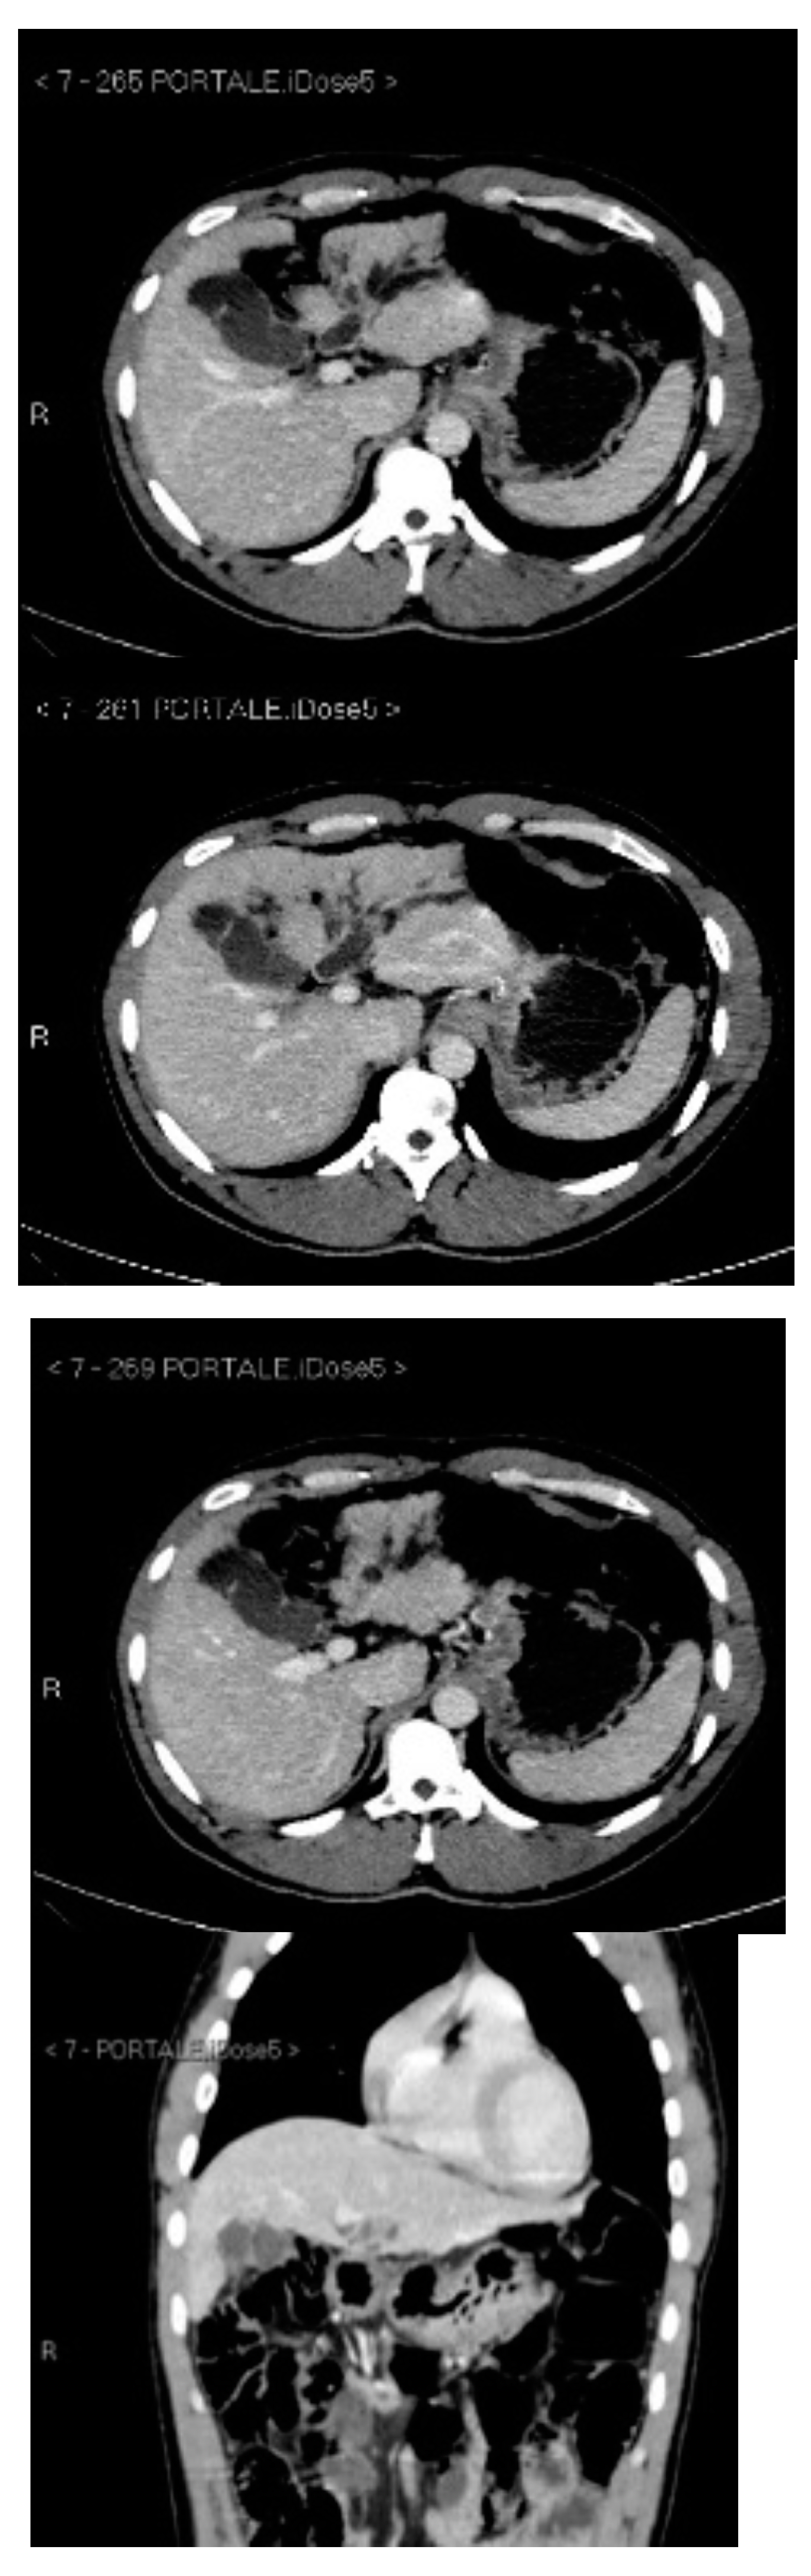

Subsequently, an upper-abdomen Computed Tomography (CT) scan and liver Magnetic Resonance Imaging (MRI) were performed (Figure 1, Figure 2, Figure 3, Figure 4, Figure 5, Figure 6 and Figure 7).

Figure 2.

CT portal phase.

A mass of 1.8 cm was detected within the biliary branch for the third hepatic segment, characterized by nodular impregnation in the arterial phase and irregular and partial washout in the portal venous phase. These findings were compatible with a heterologous lesion, although it was not possible to perform a diagnosis among HCC, intrahepatic CCA or other pathological lesions.

HCC typically has an increased arterial blood supply, so it usually shows hyperattenuation in the arterial phase and hypoattenuation in the portal venous phase, compared to the hepatic parenchyma.

Most HBDTTs should show the same enhancement pattern. However, some HCCs can show iso- or hypoattenuation in the arterial phase, with the enhancement in the arterial phase inversely correlated with the degree of blood clots and necrosis. So, hypoattenuation in the portal venous phase seems to be the most important imaging feature to distinguish HCC with BDTT from perihilar CCA [17].

In conclusion, the diagnosis of HCC with BDTT can be reasonably considered in the presence of lesions of both hepatic parenchyma and bile ducts with a cirrhotic underlined liver disease, especially if they show typical washout in the portal venous phase.